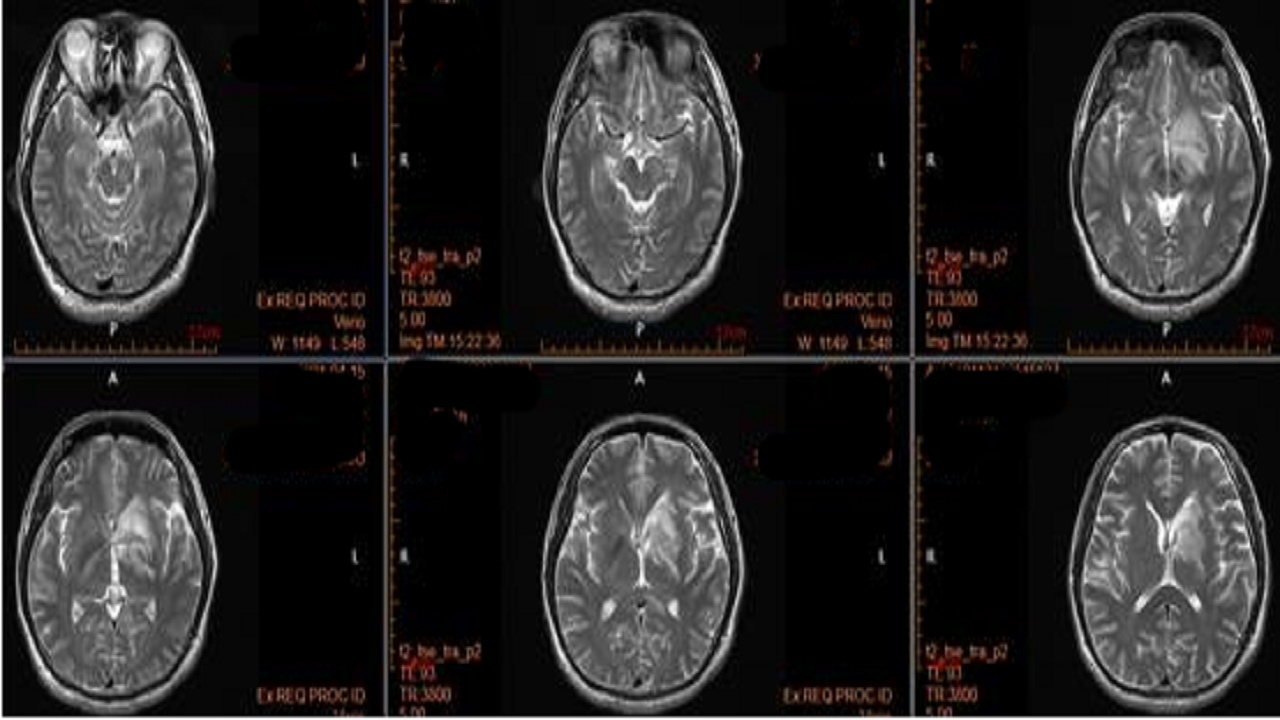

头颅磁共振平扫加增强:中脑、双侧内囊后支、胼胝体、右侧丘脑、左侧基底节区多发异常信号,炎性脱髓鞘可能。

2.MRI:病变易累及双侧皮层、皮层下及深部白质。呈长或短或混杂T1,长T2信号。DWI常呈高信号,但部分患者病变中心以低信号为主。